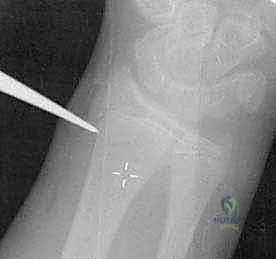

2. تقنية الرد عبر الجلد باستخدام عصا التحكم (Percutaneous Joystick Technique)

إذا لم تنجح تقنية المسامير النخاعية وحدها، يستخدم د. هطيف هذه التقنية المتقدمة.

* يتم إدخال سلك معدني رفيع (K-wire) عبر الجلد مباشرة إلى رأس الكعبرة المكسور.

* يُستخدم هذا السلك كـ "عصا تحكم" (Joystick) لتوجيه وتدوير رأس الكعبرة وإعادته إلى مكانه بدقة متناهية.

* بعد الرد، يمكن تثبيت الكسر باستخدام أسلاك تعبر موقع الكسر مؤقتاً، وتُزال بعد التئام العظم.

استخدام سلك معدني (K-wire) كعصا تحكم لتوجيه رأس الكعبرة المكسور بدقة متناهية.